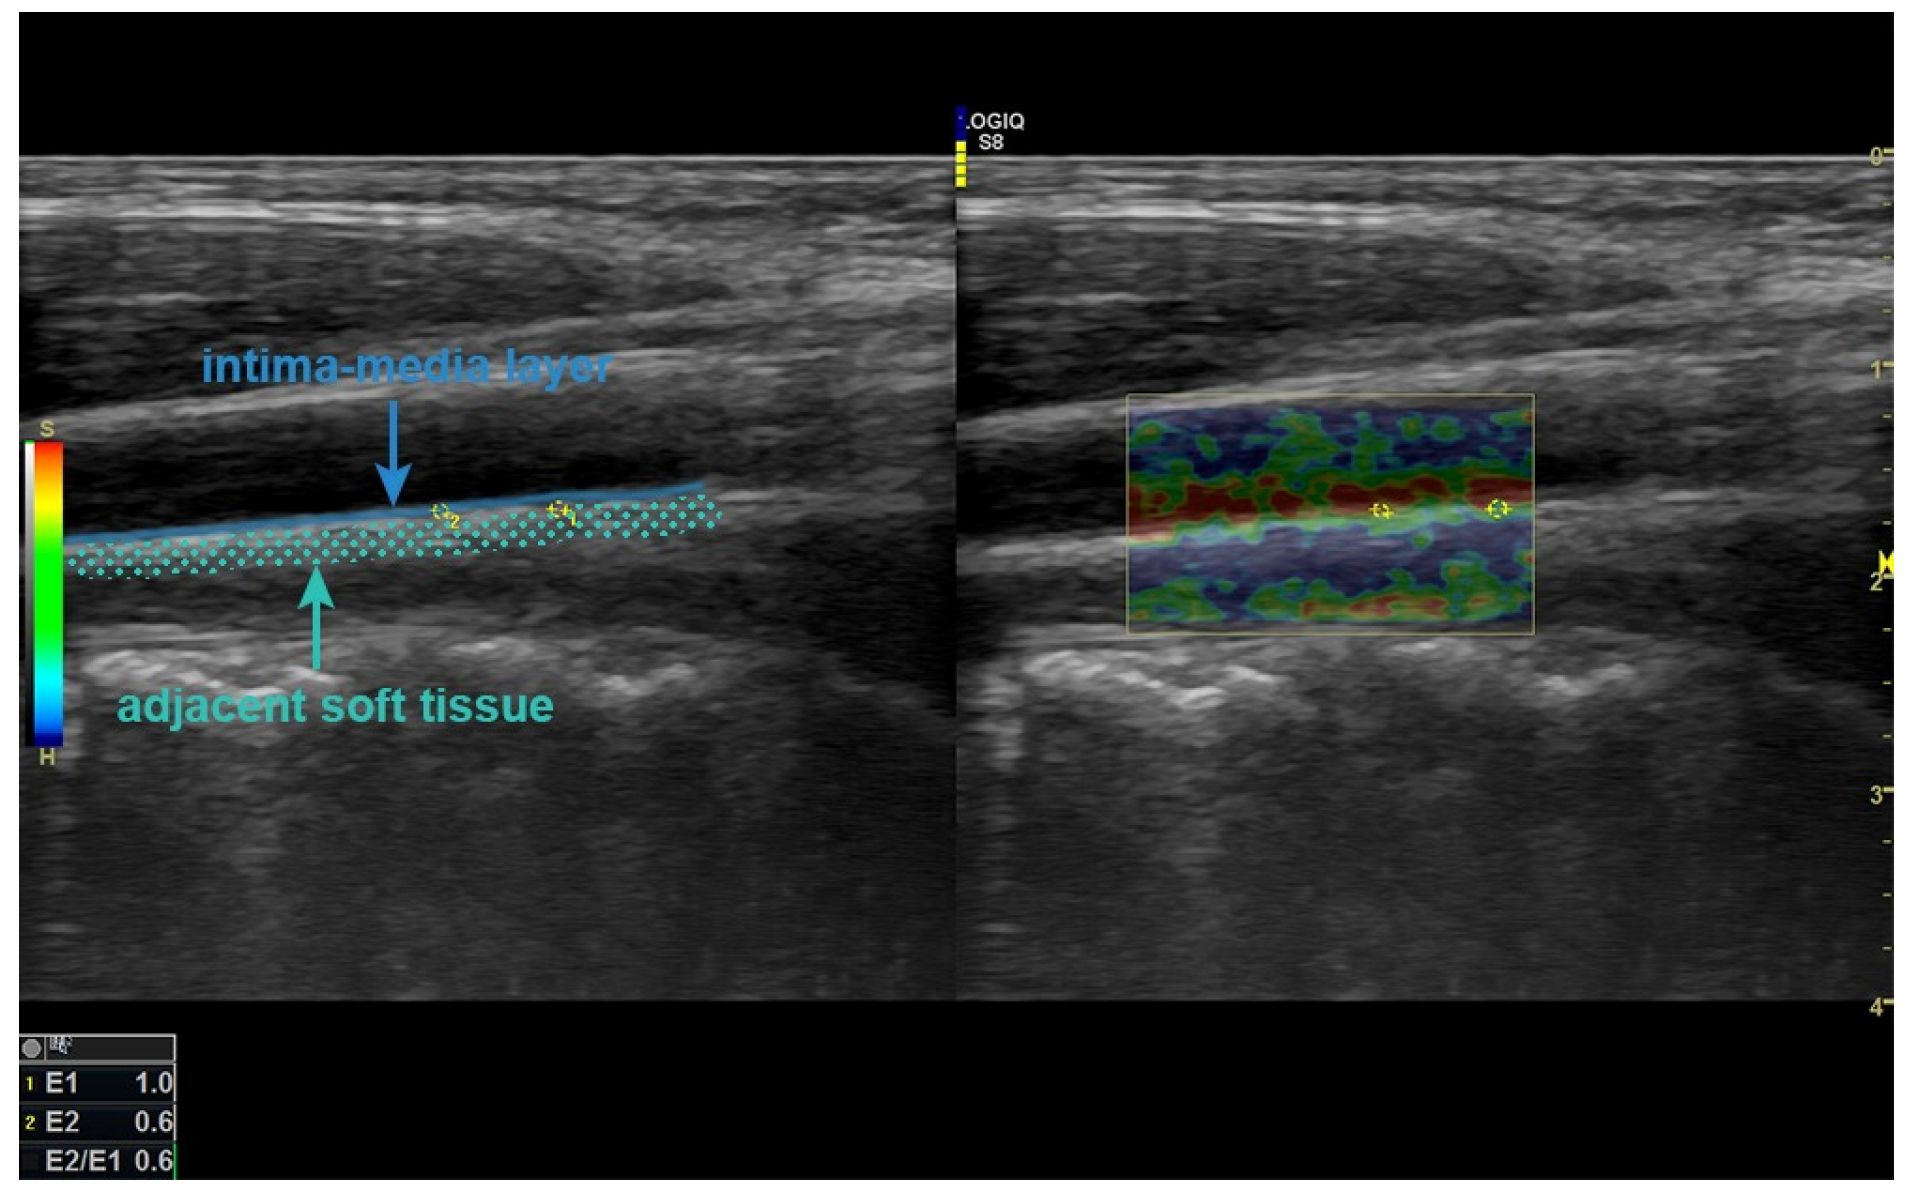

B-mode and elastographic assessments were performed by a radiologist with 6 years of sonoelastography experience using a digital sonography unit (LOGIQ S8; GE Healthcare, Wauwatosa, WI, USA) equipped with real-time tissue elastography software (Version R3). The B-mode and strain elastography (SE) images were obtained with a broad-spectrum linear transducer (9 L-D (2–8 MHz)). Since SWE was affected by vascular pulsation and could not be applied to a tiny area, such as the vessel wall, SE was applied to the carotid intima–media layer. The ultrasound gain, depth, focal points, and transducer frequency settings were kept constant in all the image scans. A color map representing tissue elasticity was superimposed on the grayscale sonographic image, with blue indicating the most elastic tissues, green-yellow indicating tissues with intermediate elasticity, and red indicating the least elastic tissues. The images obtained were stored in the archive.

The examinations were performed with the subjects in the supine position. IMT was measured on the posterior wall approximately 2 cm distal to the left carotid bulb in the longitudinal plane on the grayscale. SE was applied to the posterior wall 2 cm distal to the carotid bulb, including the intima–media layer and adjacent soft tissue. The region of interest (ROI) for measurement was sized not to exceed the carotid intima–media complex and was placed as centrally as possible. After this ROI area was set to the intima–media layer, another ROI area of similar diameter was placed in the surrounding tissue at the same depth (Figure 1). During the examination, two radiologists blinded to the patient and control groups decided the final result by consensus decision. The strain index (SI) was automatically calculated by the device software from the ratio of these two ROIs. Compared with the common carotid artery, the abdominal aorta was more difficult to assess because of its deep location and the superposition of gas distension, especially in the intestines. In addition, since the manual compression required for SE could not be achieved, sonoelastographic evaluation was not performed, and only the IMT was measured from the posterior wall at the infrarenal level.

Figure 1.

In SE examination, ROIs placed at the same depth in the intima–media layer and adjacent soft tissue on the posterior wall, 2 cm distal from the level of the left CCA bulb, are seen. SE: strain elastography, ROI: region of interest, CCA: common carotid artery.